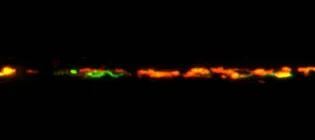

Axonal Responses of Mitochondria to Demyelination - ARMD - as evident by the abundant transport of mitochondria from the cell body to the axon (green) upon demyelination'.

Senior Clinical Research Fellow

My research in clinical and basic science aspects of progressive multiple sclerosis focuses on energy status in the central nervous system and targeting it in clinical trials.

Don.Mahad@ed.ac.uk